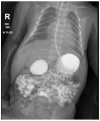

Background and Objectives: Duodenal atresia and stenosis are common causes of intestinal obstruction. Associated anomalies significantly influence early postoperative mortality, while postoperative complications impact long-term survival. Materials and Methods: Over a 13-year period from January 2010 to August 2023, a total of 74 infants and children with congenital duodenal obstruction were treated at "Grigore Alexandrescu" Children's Emergency Hospital and met the inclusion criteria. All patients diagnosed with duodenal obstruction (both instrinsic and extrinsic causes) were included. Analysed data included congenital anomalies, Apgar scores, birth weights, surgical techniques, and complications. Results: The associated anomalies included cardiac (n = 33), Down syndrome (n = 13), neurological (n = 11), pulmonary (n = 7), renal (n = 4), skeletal (n = 1), and gastrointestinal and hepatobiliopancreatic anomalies (n = 25). In total, 12 patients experienced perioperative ventilation problems. Early postoperative complications (within 30 days) occurred in 21 patients, while 6 had late postoperative complications (after 30 days). Among non-surgical complications, we noted ventilation problems, sepsis (n = 7), and pneumothorax (n = 1). Surgical complications included adhesive bowel obstruction (n = 7), incisional hernia (n = 3), peritonitis (n = 3), dysfunctional duodenoduodenostomy or duodenojejunostomy (n = 3), pneumoperitoneum (n = 5), enteric fistula (n = 3), and volvulus (n = 4). Conclusions: Surprisingly, this retrospective study revealed that an Apgar score below 8, along with neurological and pulmonary abnormalities, is associated with postoperative complications. Conversely, other congenital anomalies, low birth weight, and age at admission do not serve as prognostic factors.